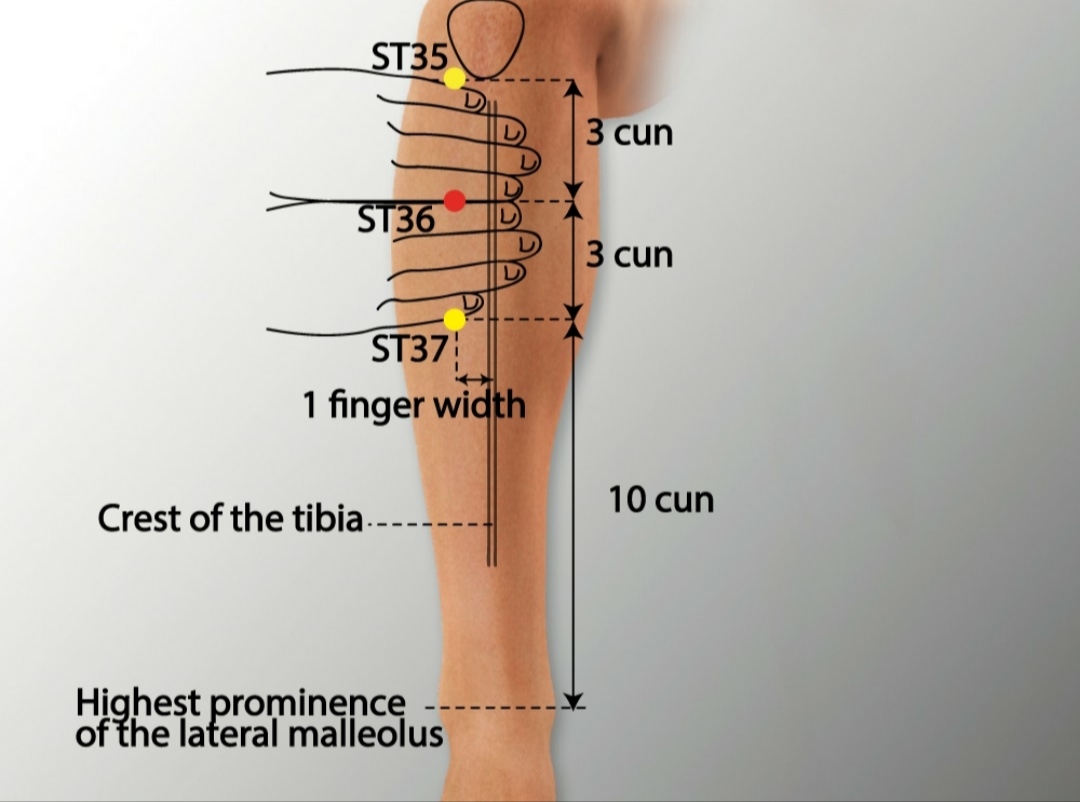

2. Hamstring or Quadriceps Strains

Muscle strains in the thigh cause pain and limited movement. Key acupoints include:

- BL36 (Chengfu): At the top of the hamstring, below the gluteal crease. Relieves hamstring pain and tightness.

- BL37 (Yinmen): Mid-hamstring, on the back of the thigh. Reduces muscle spasms and promotes healing.

- ST34 (LiangQiu): Above the knee, on the quadriceps. Alleviates quadriceps pain and improves strength.

- SP10 (Xuehai): Above the knee, on the inner thigh. Promotes blood flow and reduces swelling.

- ST36 (Zusanli): Below the knee, lateral to the shinbone. Boosts energy and supports muscle recovery.

Protocol: Treatment occurs 1-2 times weekly for 4-6 weeks, often combined with gentle stretching post-session.